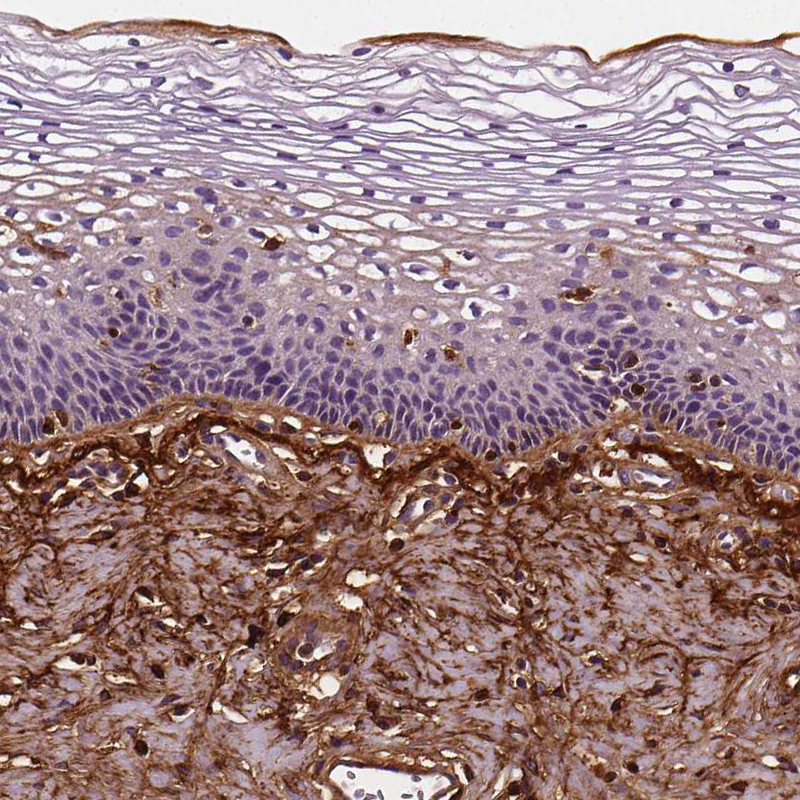

Immunohistochemistry analysis in human cervix, uterine and liver tissues using AMAb90696 antibody. Corresponding FBLN1 RNA-seq data are presented for the same tissues.